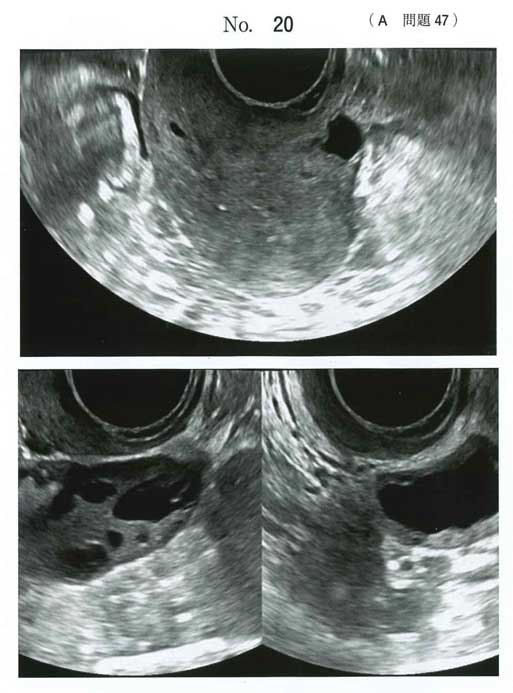

Asherman症候群

a:子宮鏡検査(ゴールドスタンダード)

アッシャーマン症候群は、流産・中絶手術などの子宮内操作により子宮内膜が損傷し、子宮壁同士が癒着・閉塞する疾患です